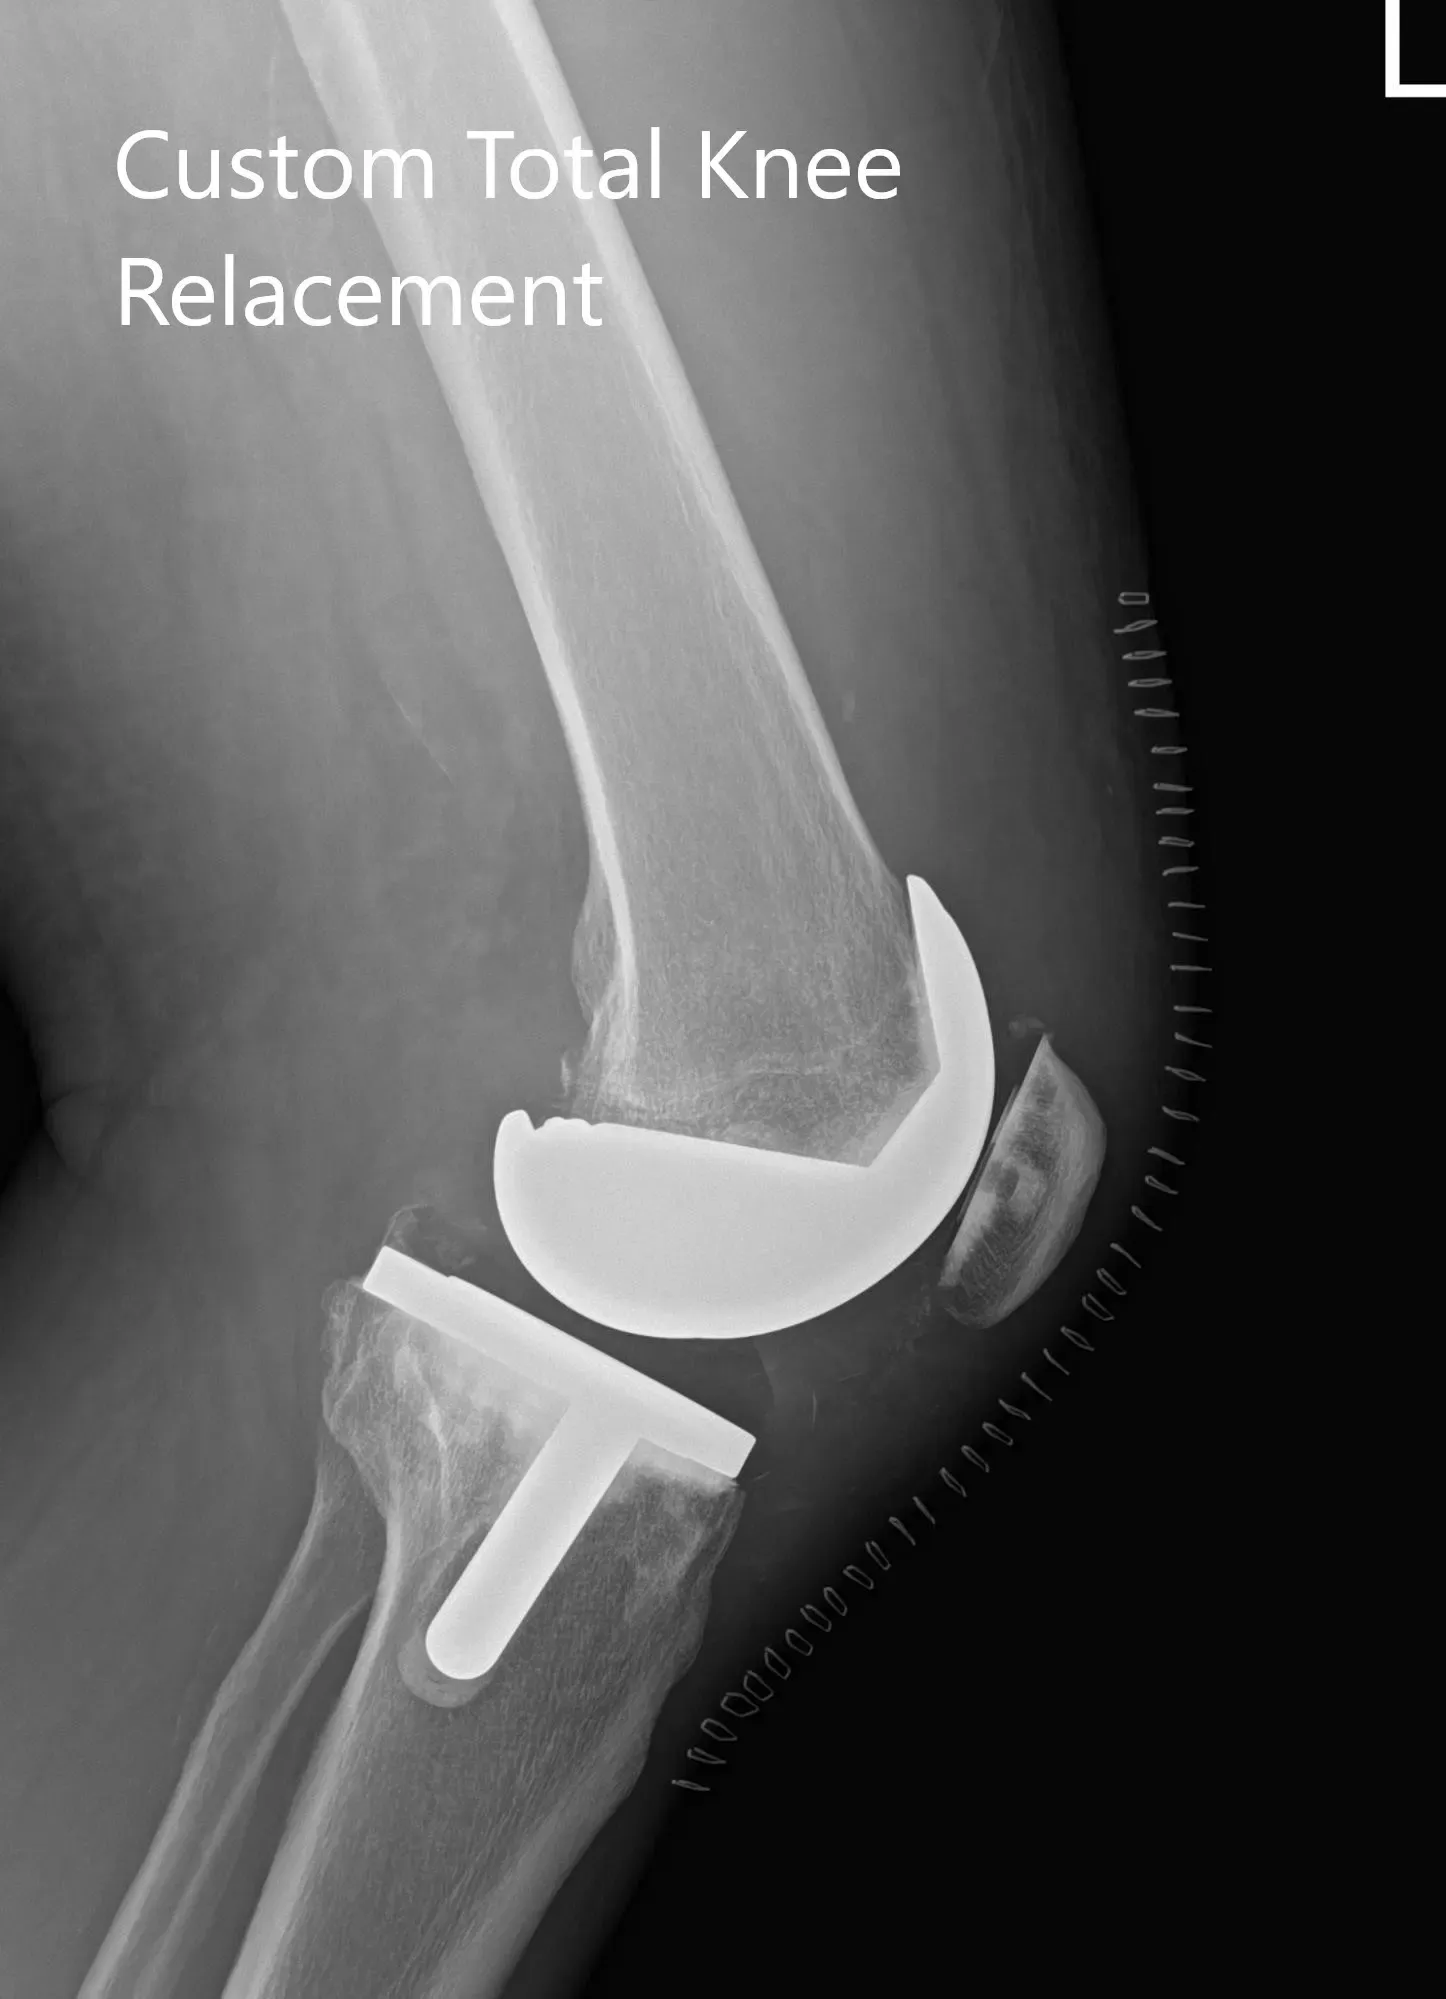

The patient had a preoperative CT scan for assessing his biomechanics and anatomy to aid in bone preserving surgery. The images were used to construct custom patient-specific implants and instruments. Unique 3D printed cutting blocks are used to preserve maximum bone. Preoperative plans are created using the 3D images to ensure correct alignment and prevent implant mismatch which is common with traditional implants.

Complete Orthopedics patient-specific surgical plan for a left custom knee replacement in a 70-year-old female.

Complete Orthopedics patient-specific surgical plan for a left custom knee replacement in a 70-year-old female (scan 2)

Implant – Custom femur with a custom tibia and patella with 8-mm polyethylene insert.